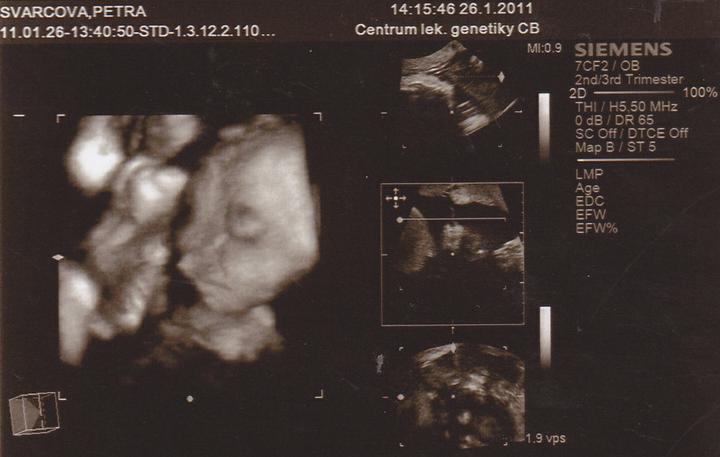

26.1.Jedu do Českých Budějovic na 4D ultrazvuk.Už se nemůžu dočkat.

Včera jsem Byla v Českých Budějovicíh.Jedno mimi váží 267g, a druhé váží 314g.A jsou to kluci.